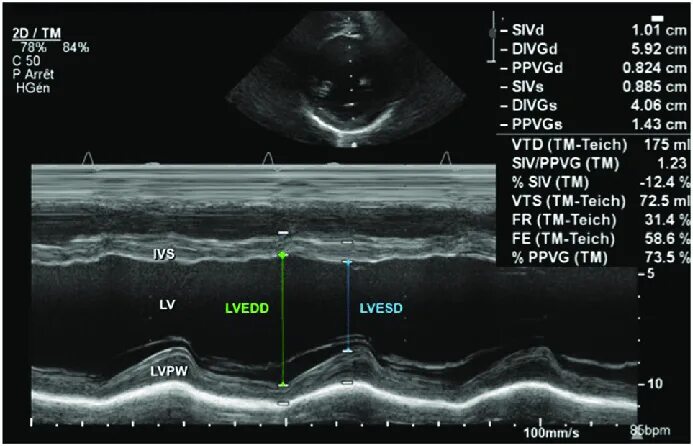

M mode